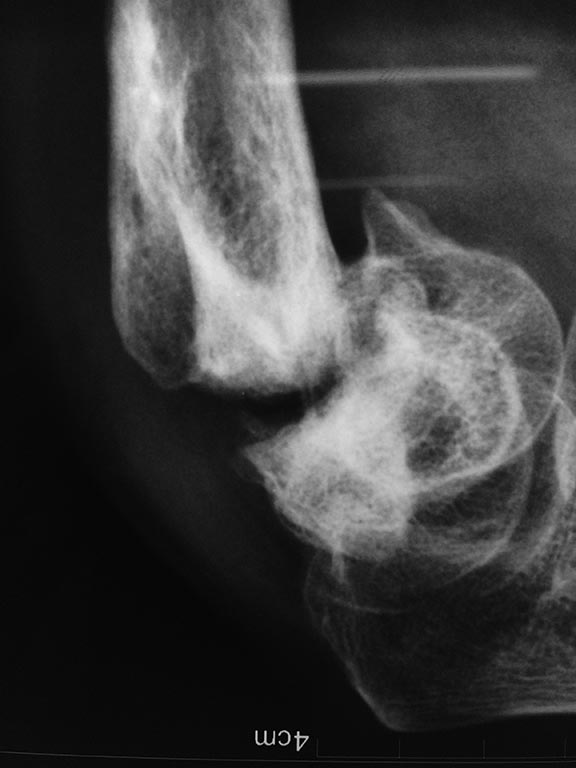

поправление ваших больных! Больной 30-35 лет получил травму 8 месяцев

тому назад с диагнозом:

Многооскольчатый перелом дистального конца правой плечевой кости.

Оперирован ургентно: открытый остеосинтез с помощью пучка спиц! сейчас

такая ситуация! на рентгенографии ложный сустав. Клиника: боль не

беспокоит, отека нет, объем движения сгибание до 30-35 градусов,

разгибание до 170 градусов. патологическая подвижность почти незаметно!

что нужно делать??? Если оперировать, контрактура сустава не

увеличивается? Какие методы реконмендуете, какой результат ожидаемый

после операции? Большое спасибо!!